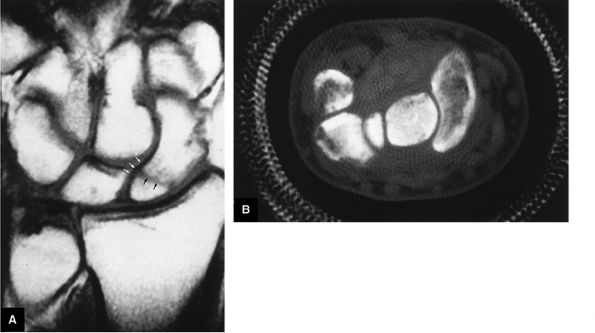

FIGURE 10.1 ● A 3D fast spoiled GRASS (FSPGR) with intra-articular contrast injected into the radiocarpal compartment. The torn lunotriquetral ligament (straight arrow) allows extension of contrast into the midcarpal compartment and the torn radial attachment of the TFC (curved arrow) directs contrast into the distal radioulnar joint. Note the superior trabecular bone detail on this image (coronal image; TR, 40.4 msec; TE, 14.5 msec; FOV, 4 cm; slice thickness, 2.0 mm; matrix, 512 × 256; flip angle, 30°).